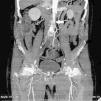

Common and applicable diagnostic methods are available for brucellosis. However, its life-threatening complications remain critical. Herein we present a 68-year-old patient who complained of leg pain for two months. At admission he had absent pulse in the left femoral and bilateral popliteal arteries. Laboratory test results were leucocytes 8700/mm3, CRP 86mg/L, and ESR 47mm/h. Abdominal CT revealed images consistent with mural thrombus in the suprarenal segment of abdominal aorta, total occlusion and hypodense thrombus material completely filling the aortic lumen through infrarenal segment extending to lumens of the caudal, bilateral common and superior iliac arteries (Figs. 1–3). No paleness, coldness or color change was detected in the lower extremities. The patient had fever, right inguinal swelling, and sweating. Abdominal CT showed an aortic thrombus and a hypodense lesion of 58mm×61mm×100mm in the right psoas muscle. The repeated Brucella STA test was positive in 1:5120 titer. USG-guided drainage of the psoas abscess was performed and a treatment with doxycycline and rifampicin was administered for three months (Fig. 4). The patient was not operated on and progressed with no clinical complaints.